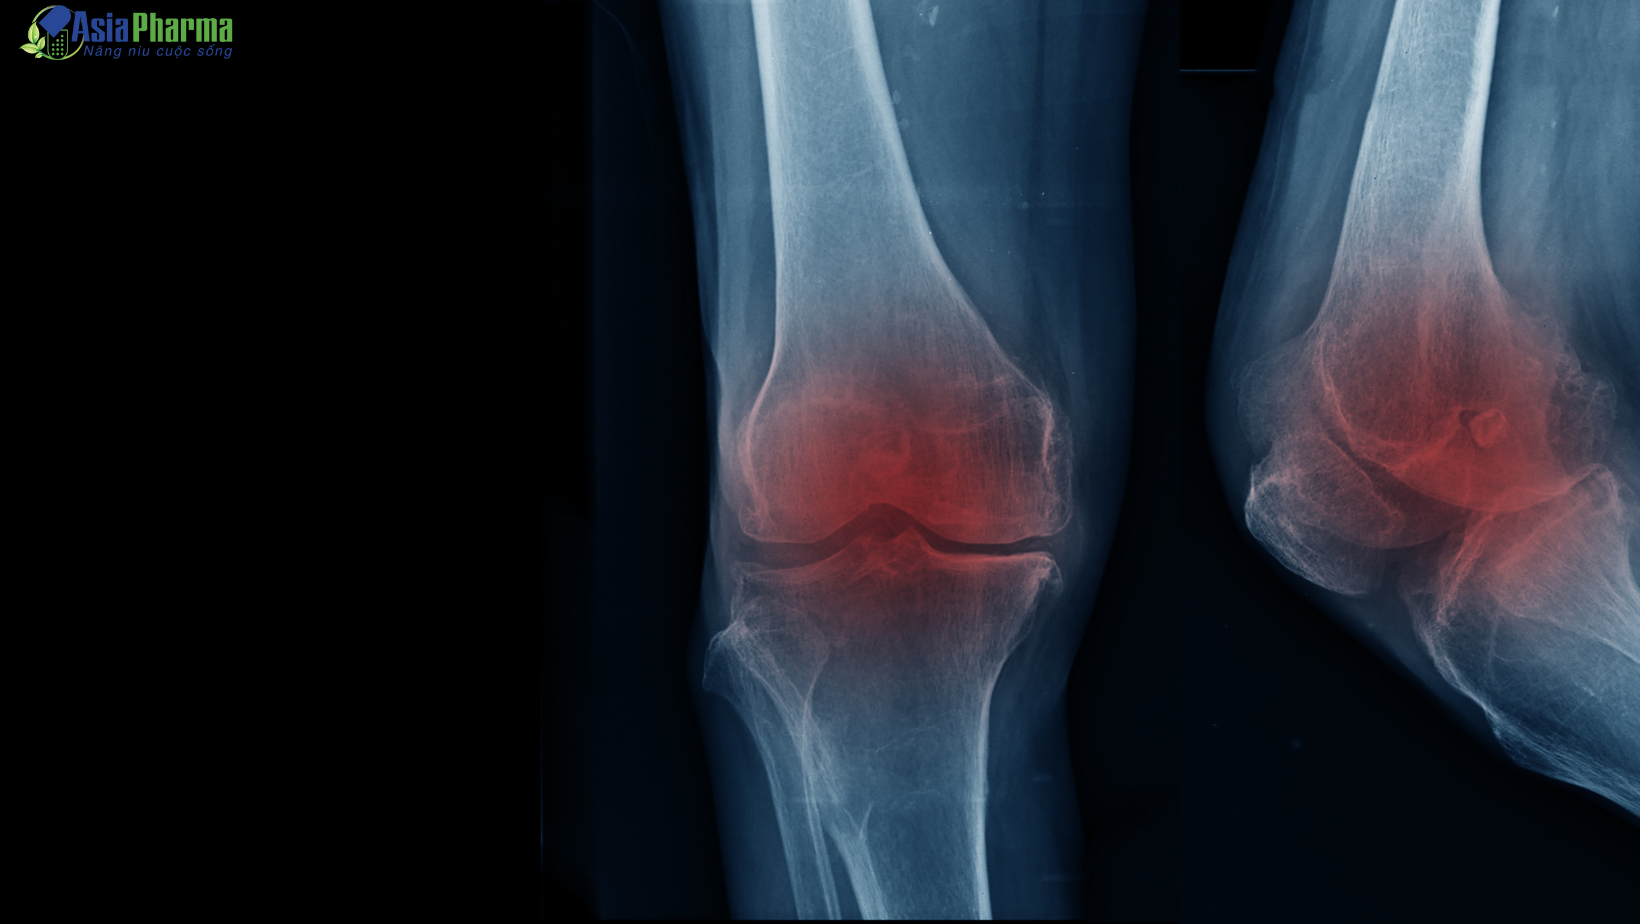

Viêm khớp là tình trạng viêm, sưng đau ở một hay nhiều khớp như: Khớp đầu gối, khớp háng, khớp vai, khớp cổ tay hoặc khớp cổ,… Đây cũng là một bệnh lý thường gặp, ảnh hưởng lớn đến khả năng vận động của khớp, khiến cho người bệnh gặp nhiều khó khăn trong sinh hoạt và thực hiện các công việc hàng ngày.

Đây là loại viêm khớp phổ biến nhất, có ảnh hưởng đến sụn khớp – lớp mô bao bọc các đầu xương, có vai trò giảm ma sát và giúp các đầu xương trượt lên nhau dễ dàng khi khớp chuyển động. Khi bị viêm, việc cử động khớp sẽ trở nên khó khăn hơn bình thường. Lâu ngày, lớp sụn sẽ dần thô ráp và mỏng đi, hình thành các gai xương, làm thay đổi hình dạng khớp hay thậm chí các xương lệch khỏi vị trí bình thường.